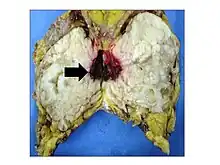

.jpg)

Malignant phyllodes tumors can behave similarly to sarcomas leading to development of blood-borne metastases.[16] Approximately 10% of phyllodes tumor develop distant metastases and this occurrence is higher (20%) in patients with histological-identified malignant tumors.[16] The most common site for distant metastases include the lung, bone, and abdominal viscera.[17] In more insidious cases, the parotid region has also been described in literature.[18]